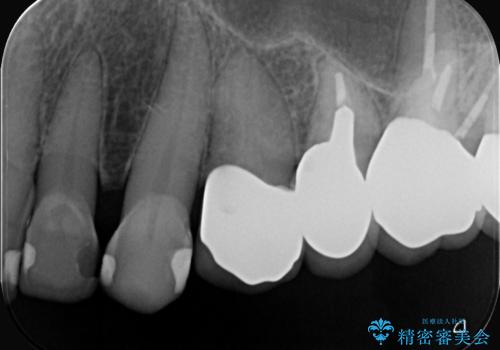

クラウンの不適により境目に汚れが溜まり、黒く見えていました。

古いクラウンを除去し、不適部位から中で広がっていたカリエスを除去したのちCRにて築造、仮歯を経てセラミッククラウンをセットしています。